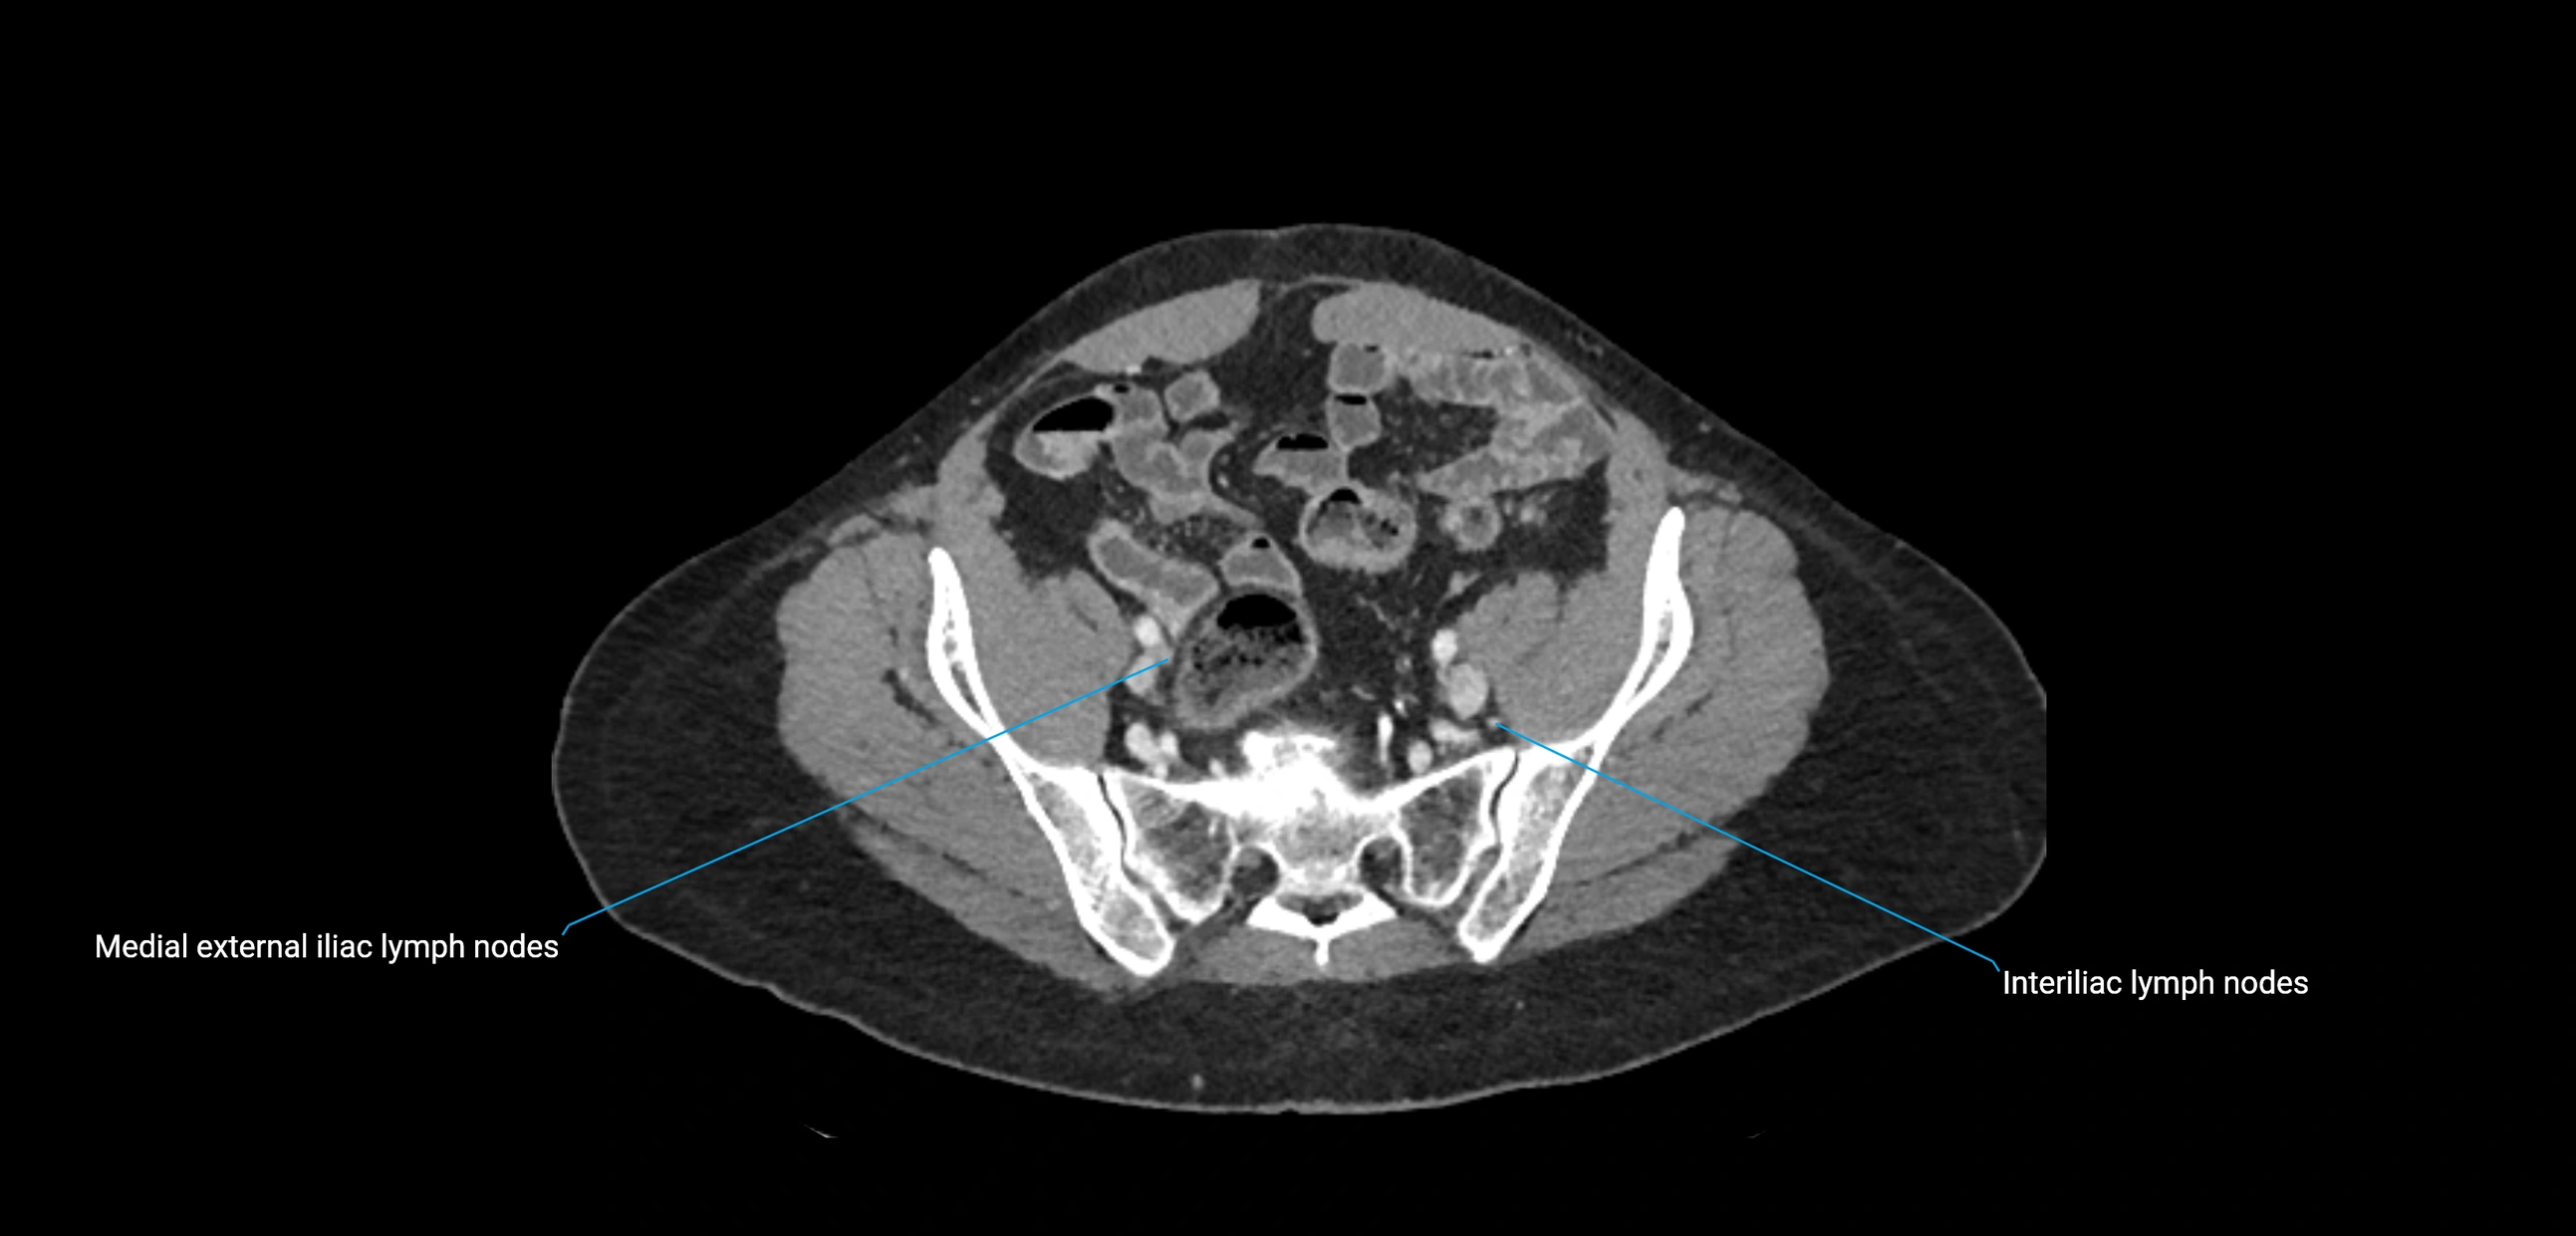

CT Appearance

CT Pre-Contrast:

• Nodes appear as soft-tissue density nodules adjacent to the aorta and IVC

• Calcification may be seen in chronic infections (e.g., tuberculosis)

CT Post-Contrast:

• Normal nodes enhance homogeneously

• Malignant nodes may show heterogeneous enhancement, central necrosis, or conglomerate formation

• Size >1 cm short axis is suspicious, though morphology and distribution are equally important